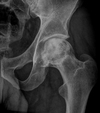

5

Q

A

Intracapsular NOF

How well did you know this?

Extracapsular NOF

Subcapital fracture (intracapsular)

Intracapsular (Garden classification)

130

Intracapsular NOF fracture Garden classification type I

131

Intracapsular NOF fracture Garden classification type II

132

Intracapsular NOF fracture Garden classification type III

133

Intracapsular NOF fracture Garden classification type IV